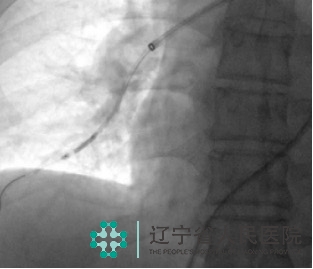

70岁的李阿姨反复出现胸闷、气短,日常需要靠轮椅出行。辗转多家医院治疗,效果不佳。来到我院,经过肺动脉CTA及超声心动图检查,确诊为“慢性血栓栓塞性肺动脉高压”,超声心动图提示重度肺动脉高压,右心室显著增大,收缩功能差,双肺部血管血流灌注缺损,病情非常严重。

经过慎重的术前评估,我们为其实施了经皮肺动脉球囊成形术,术中寻找到了严重狭窄甚至闭塞的肺动脉,进行有效球囊扩张。术后,患者活动耐量明显改善,胸闷、憋气症状得到缓解。

肺动脉球囊成形术的机理是通过肺血管小球囊扩张的方式改善阻塞血管的血流,达到重建肺循环的目的,对于无法耐受开胸手术的患者非常适用,治疗后,患者活动耐量可明显提高,部分患者可停用靶向药物。